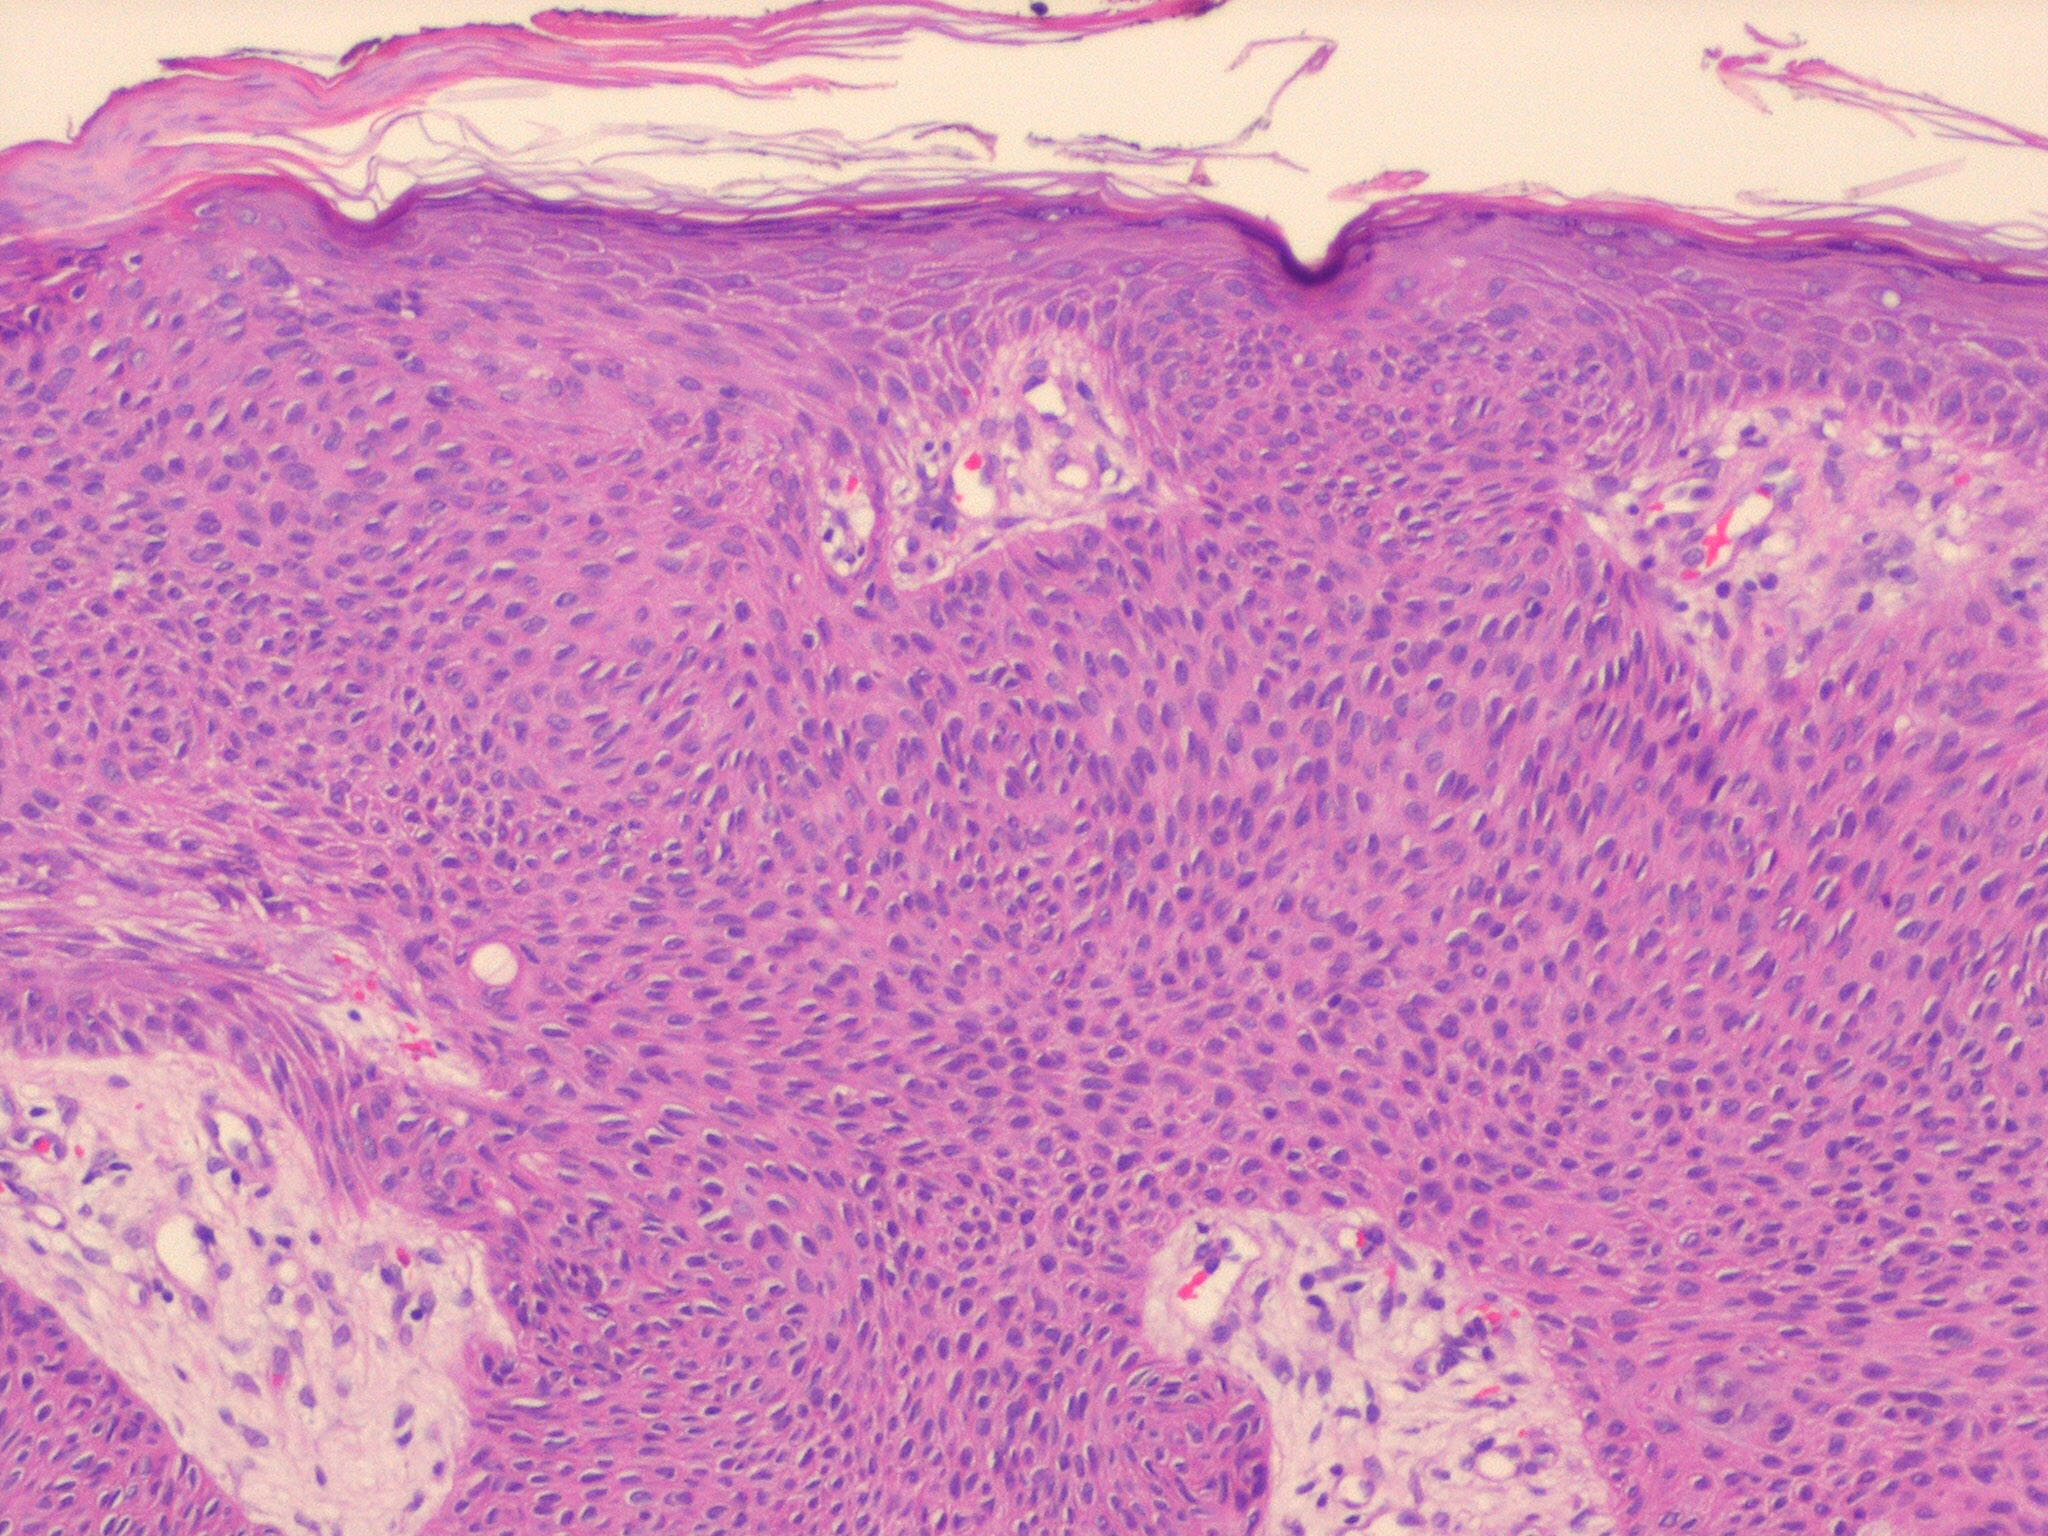

Hidroacanthoma_simplex = الشوكوم العرقي البسيط

OLYMPUS DIGITAL CAMERA